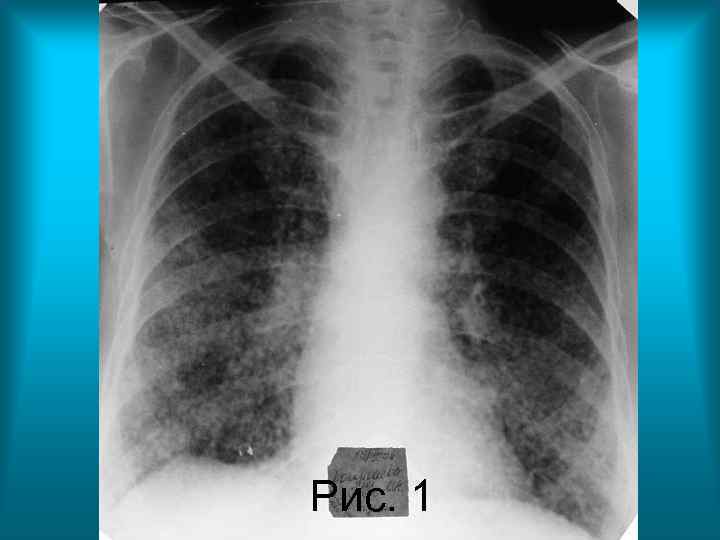

Пациентка К. 70 л. Диагноз: Диссеминированный туберкулез легких. Бронхогенная диссеминация. Рис. 1. Обзорная рентгенограмма органов грудной полости в прямой проекции. Грудная клетка цилиндрической формы. Определяется тотальная мелкоочаговая диссеминация с преимущественным расположением очаговых теней в средних и нижних поясах легочных полей. Корни легких расширены, структура их сохранена. Правый купол диафрагмы деформирован плевродиафрагмальными спайками.

Рис. 1 Н. С. Воротынцева. С. С. Гольев Рентгенопульмонология